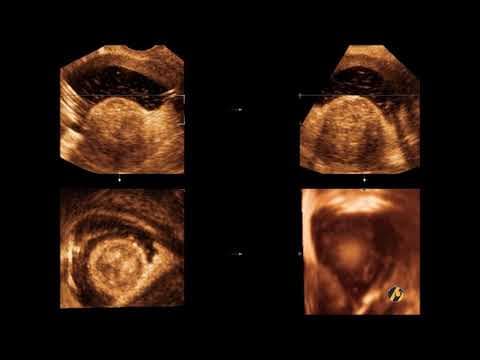

• 2D ultrazvuk = standardna ravna slika (sve poliklinike imaju) • 3D ultrazvuk = trodimenzionalna slika fetusa (detaljnije vide se anomalije) • 4D ultrazvuk = 3D slika u pokretu (vidite fetus kako se mijenja u realnom vremenu) • 5D/HD Live ultrazvuk = najnaprednija tehnologija s detaljima kao fotografija U Poliklinici Harni koristimo 3D, 4D i 5D ultrazvuk, što nam omogućava ranom otkrivanju anomalija i pružanju roditeljima jasne slike bebe prije poroda.